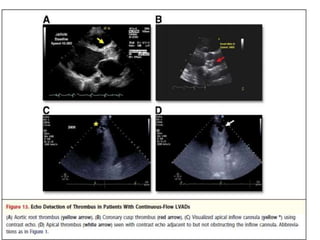

• Other LVAD dysfunction/related complications:

• In addition to thrombosis of the LVAD cannula,

• Rarely, LVAD support is associated with aortic

root thrombosis secondary to blood stasis in

the setting of prolonged AV closure.

• In persistent closed AVs, laminated thrombus

may form more commonly or more

prominently in the noncoronary cusp,

presumably due to lack of coronary artery

runoff.

• Thrombus can also form in the cardiac apex.

• Echo, especially with the use of contrast, can

aid in the identification of apical thrombus,

which can be difficult to detect in the

presence of an apical inflow cannula